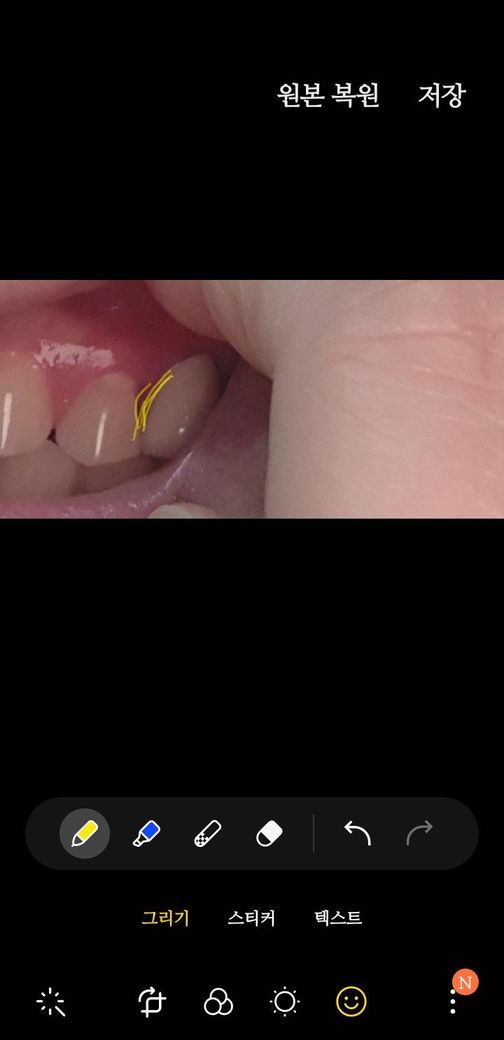

임플란트 보철을 오늘 껴보니 앞니와 공간이 까맣게 많이 생기는데요 제가 앞니가 썪어서 잇몸이 사라져서 저렇다는데요 그럼 보철 모양을 윗부분을 봉긋하게 만들면 되지 않나요? 모양변경이 어렵다고 주장하시는데 답답하네요

• 2번 째 사진